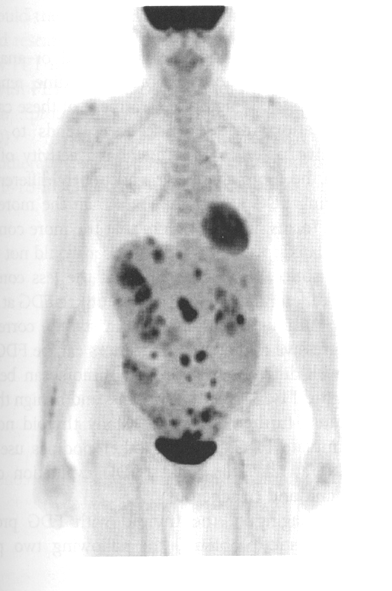

what does this image show

melanoma (diffuse) whole body

ovarian cancer with extensive METS to where

peritoneal cavity

ovarian cancer